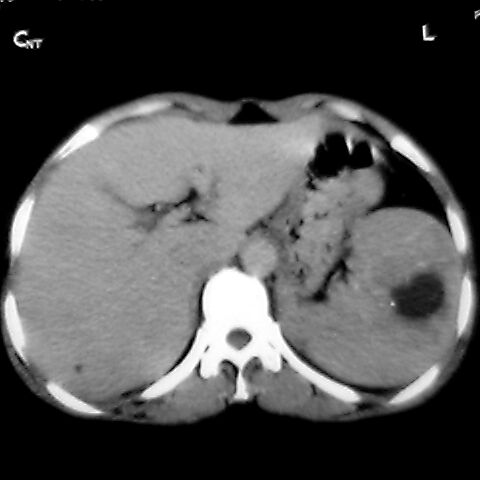

标题: [原创]CT4167脾占位。请大家帮忙会诊。

女 48岁 食道癌术前体检发现脾占位。

1肝右下叶小囊肿2右肾上极囊肿或错构瘤3脾脏不典型血管瘤可能性大.

脾脏低密度灶伴钙化,增强化明显,中心见液化坏死灶,强化延时明显。考虑血管瘤。转移瘤待排。

1,脾血管瘤。2,右肝,右肾小囊肿。